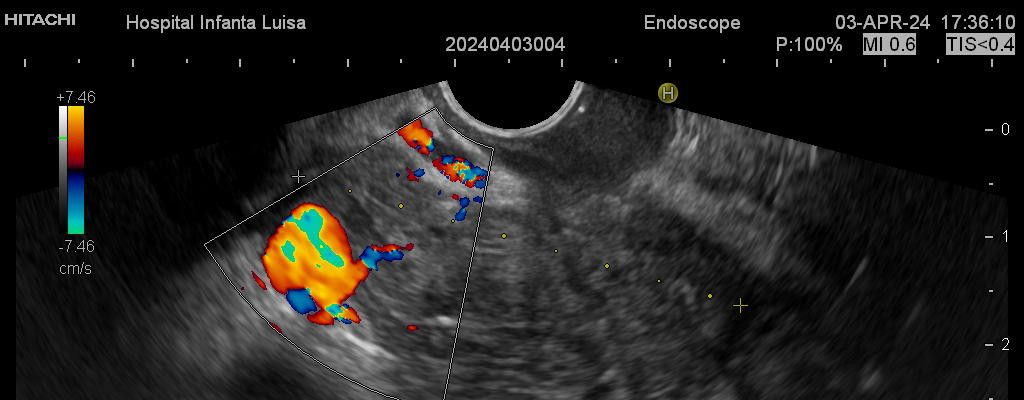

Ecoendoscopia

La Ecoendoscopia o Ultrasonografía endoscópica (USE) consiste en la exploración del tracto digestivo superior (principalmente), o de los últimos centímetros del tracto digestivo inferior (recto, generalmente), con un tipo de endoscopio especial que se llama ecoendoscopio.

La Ecoendoscopia, como su nombre indica, combina dos tipos de técnicas: la endoscopia y la ecografía, pues nos aporta simultá…